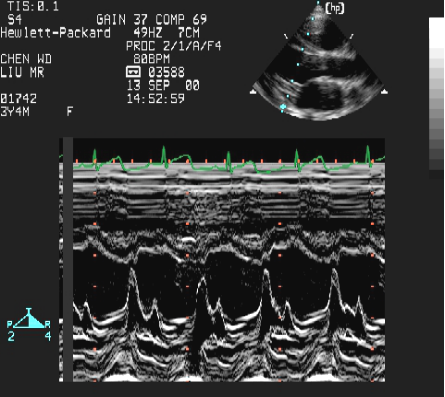

室间隔缺损:超声心动图表现

左房增大 左室增大

(室间隔缺损的间接征象)